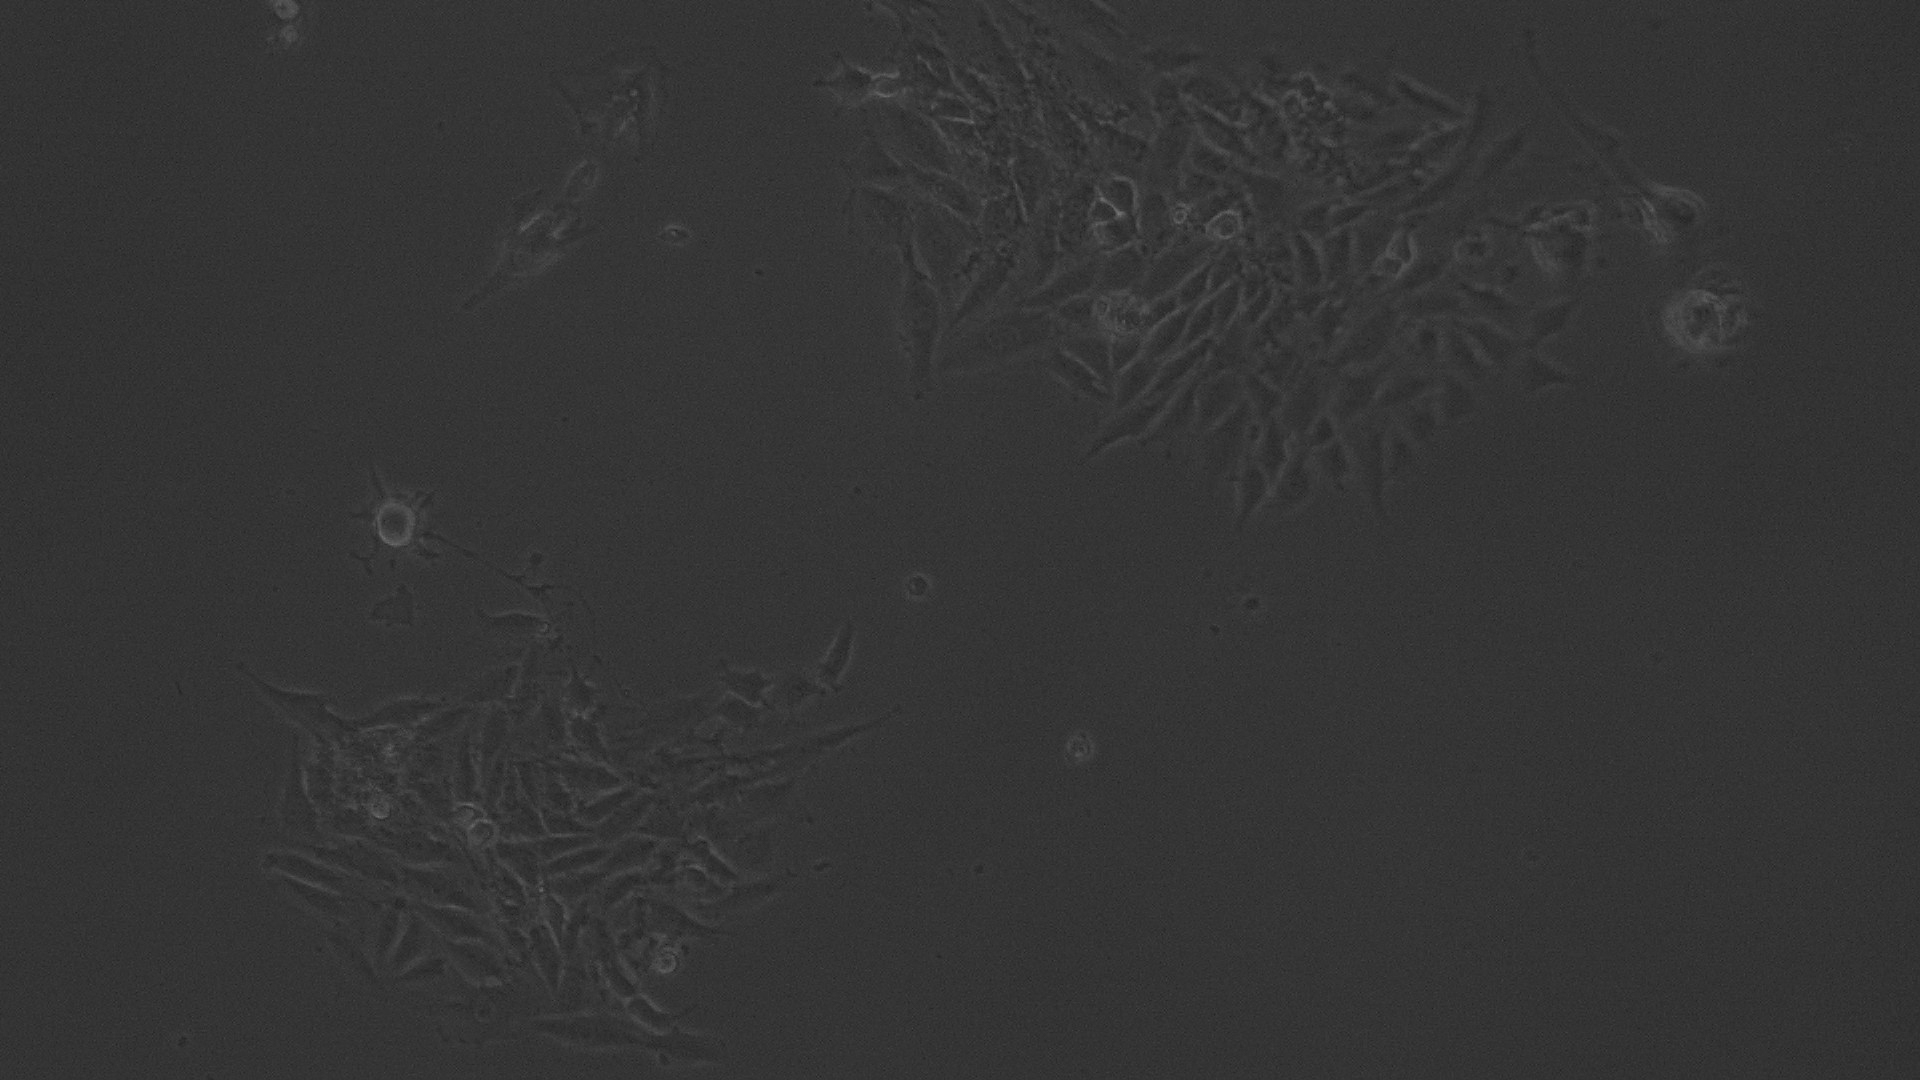

The entire plate was observed at an interval of every 24 h; up to 72 h in an inverted phase-contrast tissue culture microscope (Labomed TCM-400 with MICAPSTM HD camera) and microscopic observations were recorded as images. Any detectable change in the morphology of the cells, such as rounding or shrinking of cells, granulation, and vacuolization in the cytoplasm of the cells, were considered as indicators of cytotoxicity.

Fig. 5: Morphological changes showing inhibition of Hela cell lines by different concentrations of ethanolic extract of leaves of Pothos scandens. a: -ve control (95% ethanol), b: 6.25 µg/ml, c: 12.5 µg/ml, d: 25 µg/ml, e: 50 µg/ml f: 100 µg/ml

In vitro anticancer actiivity of ethanolic extract of leaves of Pothos scandens Linn. was evaluated against HeLa and MCF 7 cell lines. The viability of cells was evaluated by direct observation of cells by an Inverted phase contrast microscope and MTT assay method. The morphological changes in HeLa and MCF 7 cells after treatment with the extract and standard doxorubicin are shown in fig. 5, 6, 7 and 8. The IC50 values are shown in table 4.